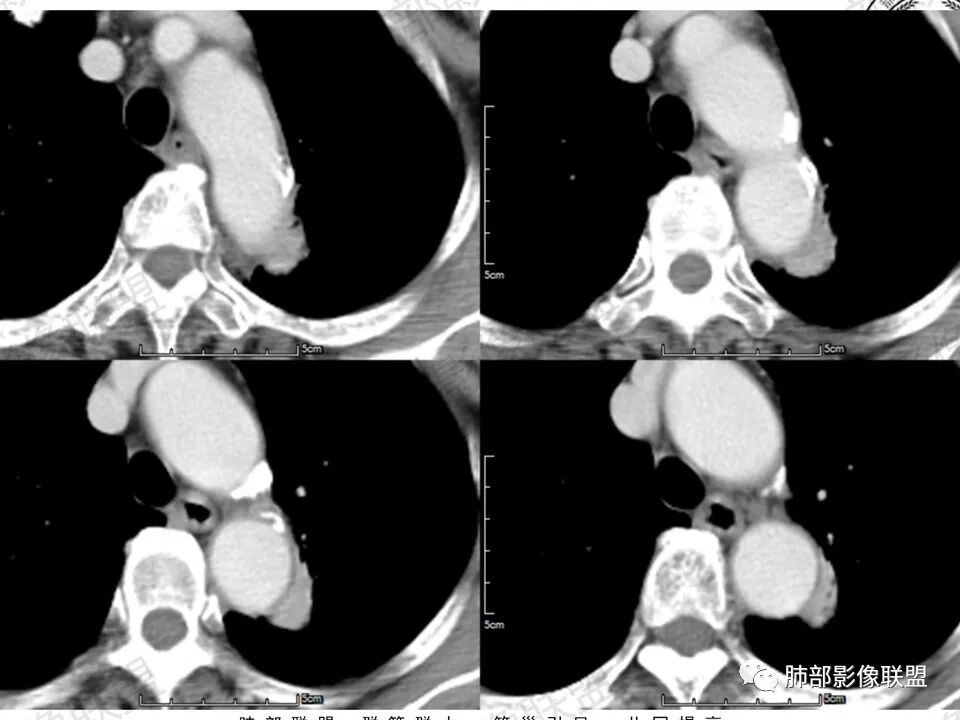

一、病例资料

病史无什么特殊性,老年女性。1、主动脉弓壁钙化2、长条影主要趴在弓部向胸主动脉位置。3、增强延迟明显强化,接近母血管。4、长形影周围条索影(纤维化)。敢在大血管长趴着睡的关系并接近强化,考虑主动脉假性动脉瘤?附壁血栓?周围局部包裹纤维化。

降主动脉旁不规则肿块,形态不规则,边缘平直,收缩,宽基底与主动脉相贴,周围脂肪间隙消失,病变内上缘可见支气管包绕?还是空泡?考虑肺内来源,病变平扫密度均匀,增强后动脉期低强化,静脉期和延迟期等同血管强化,局部血管壁增厚,上部可见主动脉发出血管供血,考虑1:肺隔离症2:炎性肉芽肿,3:腺癌

胸降主动脉旁片状软组织密度影,部分边缘欠规整,周围可见索条影,增强后均匀强化,并呈渐进性强化,考虑炎性肉芽肿性病变

降主动脉旁不规则肿块,形态不规则,宽基底与脏层胸膜相贴,局部胸膜掀起,增强渐进性明显强化,胸膜来源考虑STF,鉴别炎性肉芽肿病变病变

老年女性,左肺上叶纵膈旁不规则结节,可见局限性膨凸,边缘见磨玻璃成分,边界清晰,强化明显,考虑恶性,支持腺癌可能性大!

左肺上叶靠主动脉旁实性结节,宽基底相连,密度均匀,平直边及尖角,边缘长索条及胸膜牵拉,明显持续强化,考虑慢性炎症,鉴别腺癌

左肺上叶不规则肿块,与斜裂胸膜宽基相连、紧贴,斜裂增厚,增强持续、明显强化,并见血管穿行,边缘部分平直,部分膨隆,部分层面病灶边界不清,考虑慢性炎症,鉴别腺癌

主动脉旁软组织影,边界不清,内见含气支气管,周边不干净,考虑肺内来源病变,明显延迟强化,考虑慢性炎性肉芽肿病变,慢性炎症或结核。

老年女性,主动脉弓旁占位,宽基底与主动脉弓相贴,增强延迟均匀强化,内见血管穿行,周围见血管贴边,考虑胸膜来源肿瘤:SFT可能。鉴别慢性炎性病变

主动脉旁软组织影,边界不清 部分边缘平直,部分毛刺,内见血管影,周边不干净,考虑肺内来源病变,明显延迟强化,考虑良性病变,慢性炎症或IMT OP,鉴别腺癌。

老年女性。左上肺主动脉弓旁类椭圆形实性密度影,边缘有彭隆、局部平直,浅分叶;边界大部分清晰,少许须状影,少许边界清晰磨玻璃影;周围肺纹理欠干净,少许细线影;与临近胸膜面宽基底相连,一侧胸膜牵拉凹陷。增强后明显均匀强化。我考虑炎性病灶,建议抗炎治疗后短期复查,排除恶性可能。少许的磨玻璃让人心慌,腺癌也是很有可能,主要就是持续的明显强化,不太符合。

左肺上叶尖后段主动脉旁结节影,病灶紧贴主动脉,分界清,增强扫描渐进性强化,内见血管影,考虑慢性炎性病变。鉴别SFT.

老年女性,体检发现左上肺主动脉弓旁占位,脂肪间隙清晰,边缘部分光滑、部分毛糙,似有毛刺、分叶,似有边界清楚的GGO,内部大部密度均匀,有条索状低密度(支气管粘液栓?),增强检查见均匀明显强化,延迟强化明显(CT值增加近80Hu)。边缘见支气管提示肺内病变。整体考虑炎性可能,炎性病变的强化似乎是以动脉期明显,本例延迟强化明显,延迟强化明显的病例可能有:PSP、类癌、淋巴上皮瘤样癌、炎性病变?…………似有分叶及病灶边缘GGO,注意鉴别腺癌。